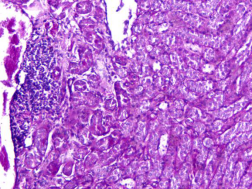

PAS檢測實驗報告【小鼠腎】

對組織樣本進行PAS染色。

樣本:小鼠腎

圖1 PAS染色示意圖100×

四、實驗結論

PAS反應陽性物質 紅色或紫紅色

細胞核 藍色

細胞質 深淺不一的紅色

糖原染色是病理學中常規的染色方法之一,氧化劑能氧化糖類及有關物質中的1,2-乙二醇基,使之變為二醛,醛與Schiff試劑能結合成一種品紅化合物,產生紫紅色。PAS技術常用來顯示糖原和其他多糖,該染色液不僅能夠顯示糖原,還能顯示中性黏液性物質和某些酸性物質,以及軟骨、垂體、霉菌、真菌、色素、淀粉樣物質、基底膜等。